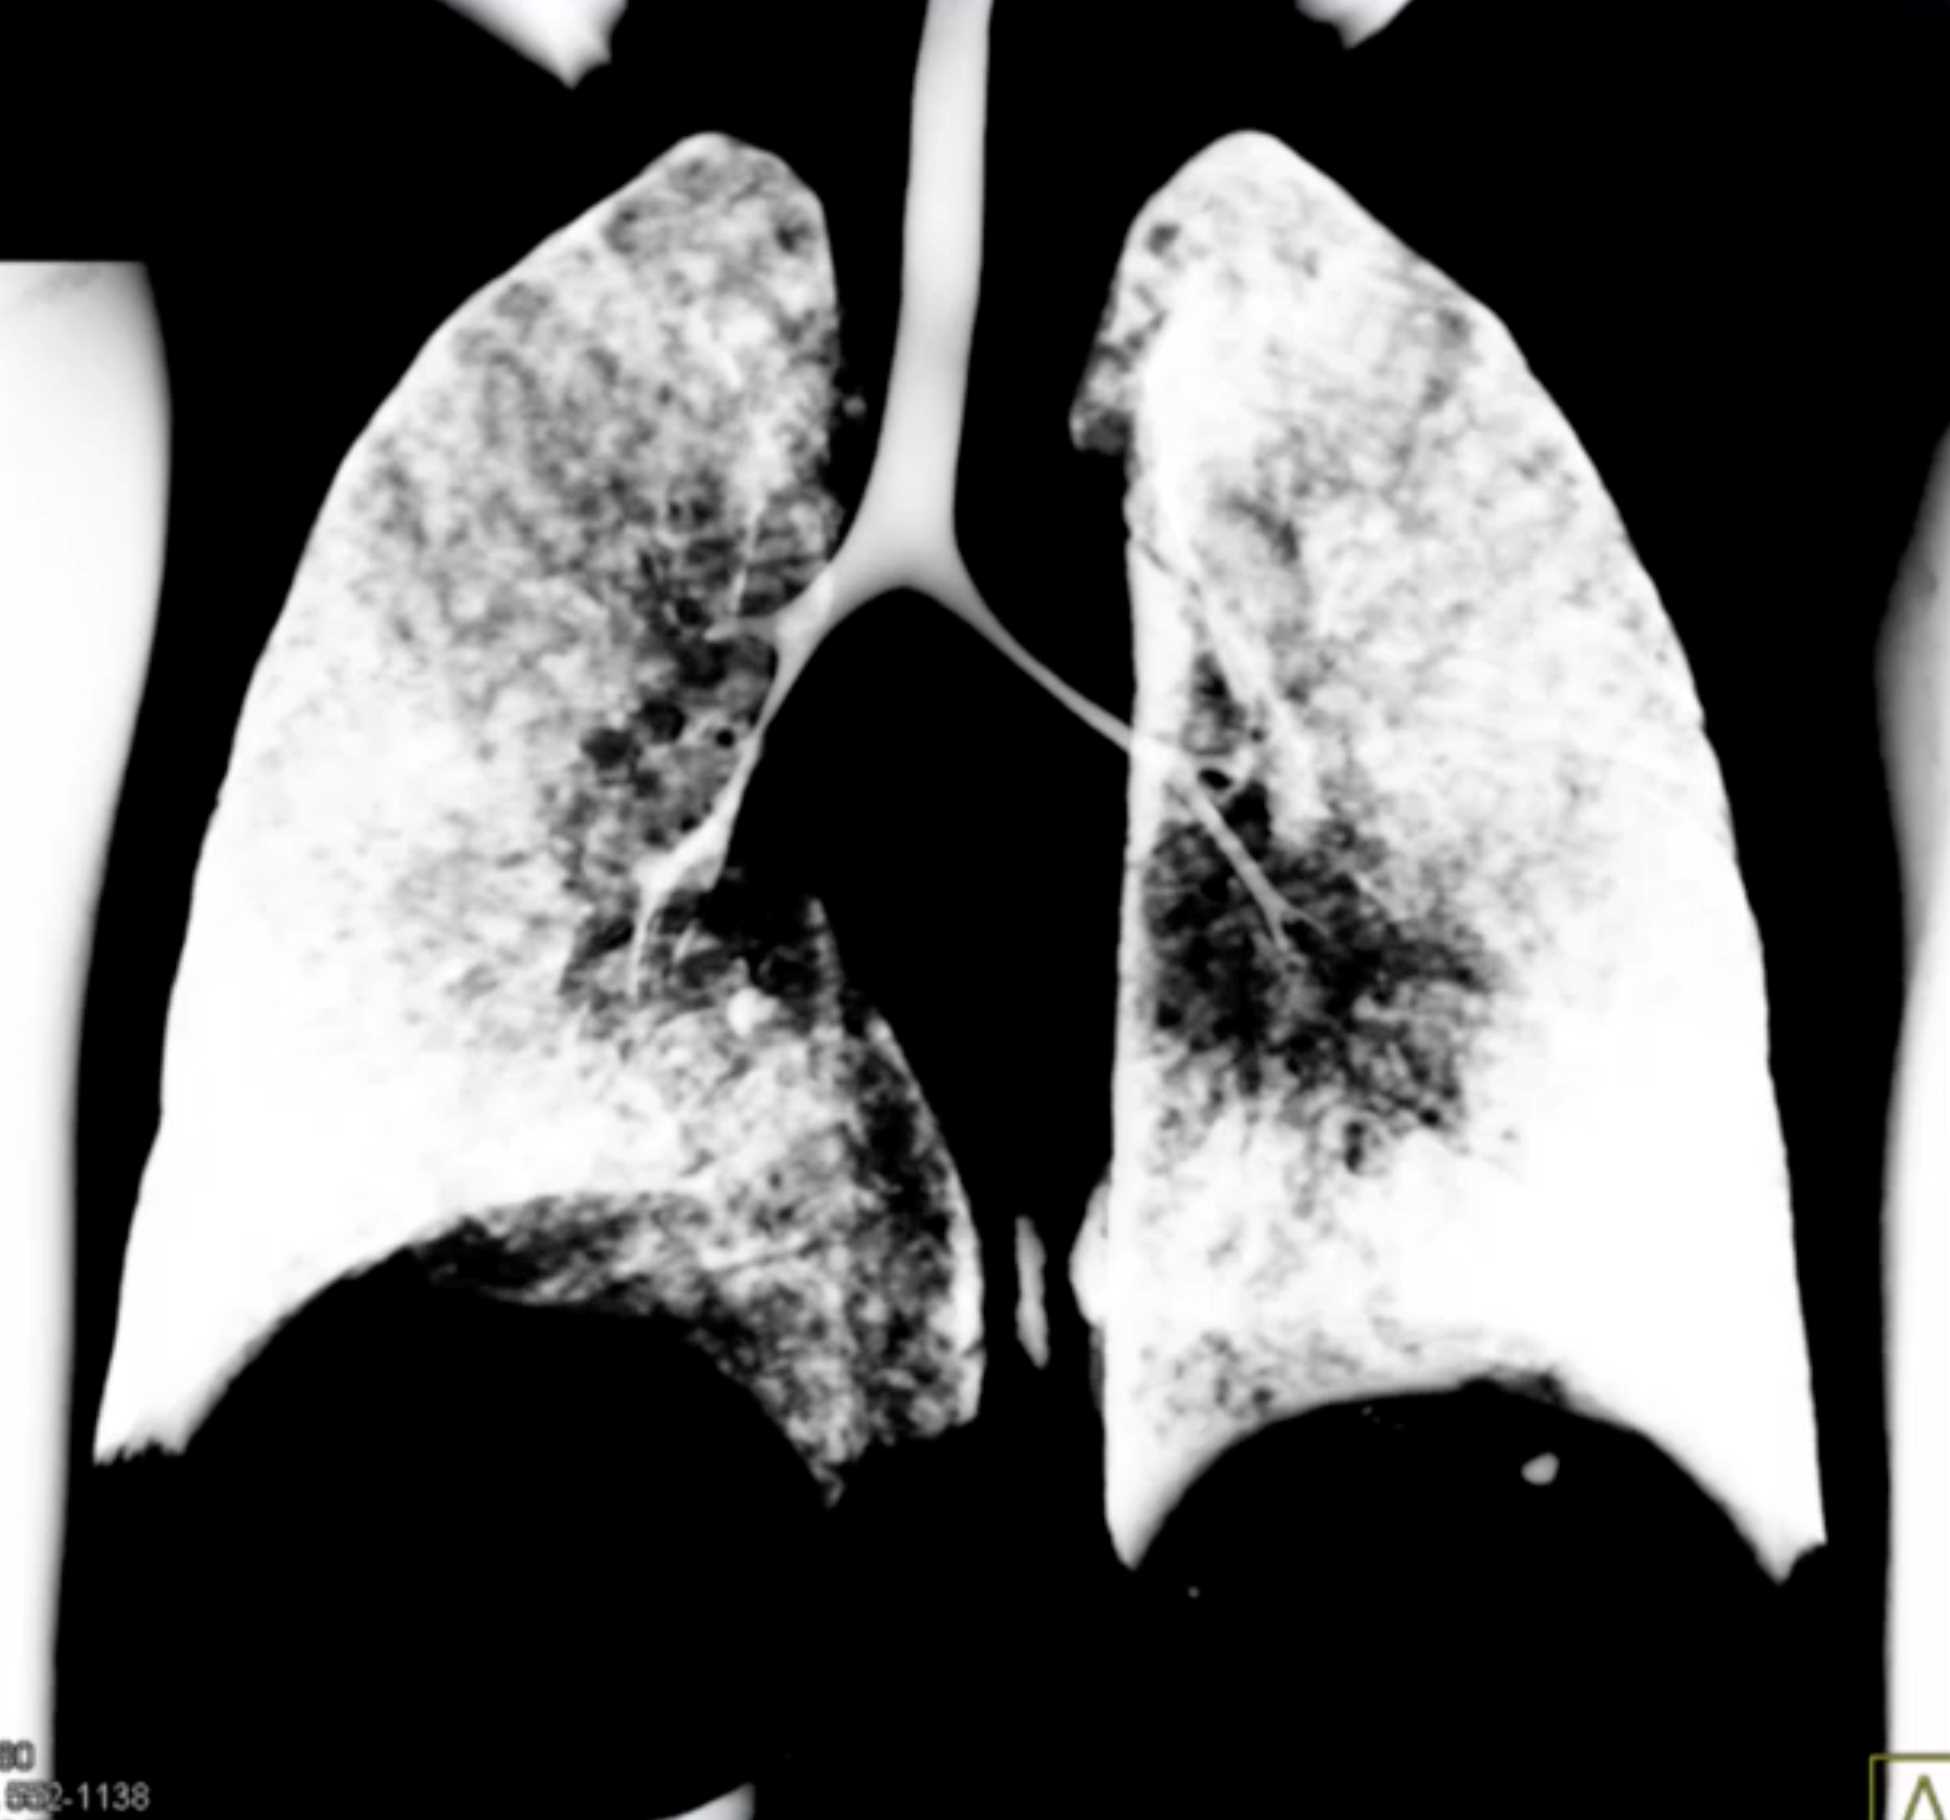

Histoplasmosis and Normal Thymus